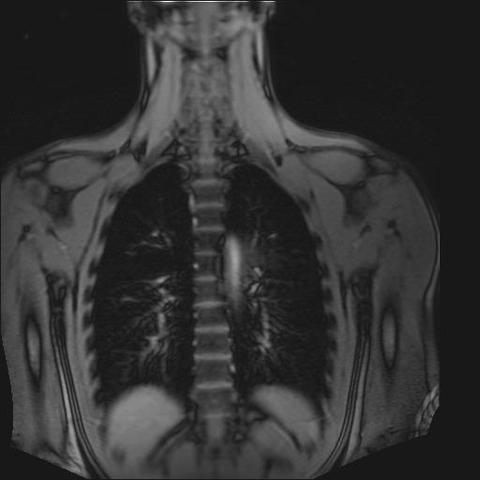

Wer damit Probleme hat sollte das Personal vorher darauf ansprechen. Die MRT der Hüfte ist mittlerweile ein sehr gutes bildgebendes Verfahren um strukturelle Veränderungen der Hüfte und anderer Gelenke frühzeitig zu erkennen. Besser als beim Röntgen und bei einer Computertomographie können bereits kleinste Veränderungen von.

Die MRT der Hüfte ist mittlerweile ein sehr gutes bildgebendes Verfahren um strukturelle Veränderungen der Hüfte und anderer Gelenke frühzeitig zu erkennen.